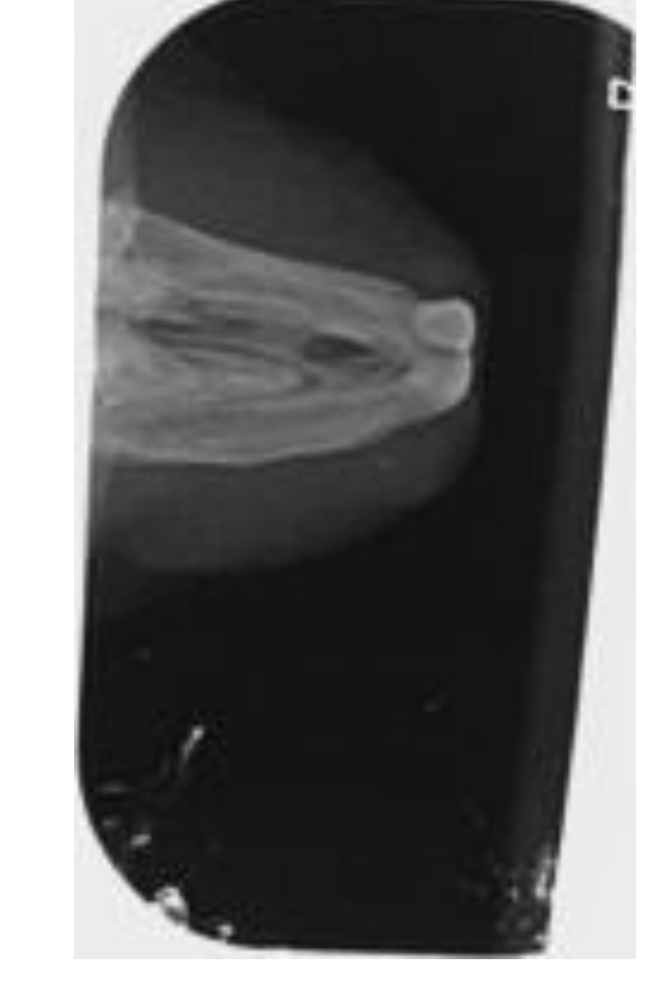

Hallo, Santiago wurde inzwischen unter einer Gasnarkose geröntgt- und hat es überlebt. *nicken* Die Tierärztin meinte, dass er ein Odontom (wuchernde Zahnwurzel?) hat, aber dies noch nicht so schlimm sei, dass man die OP riskieren würde. (Da müsste man von außen an den Kiefer ran)

Ich hänge mal die Röntgenbilder an- leider erkenne ich dort garnichts. Kann einer von euch etwas dazu sagen, wie schlimm es ist?

82BA218B-5901-462A-94A2-C942F4978031.jpeg

82BA218B-5901-462A-94A2-C942F4978031.jpeg (93.43 KiB) 2172 mal betrachtet